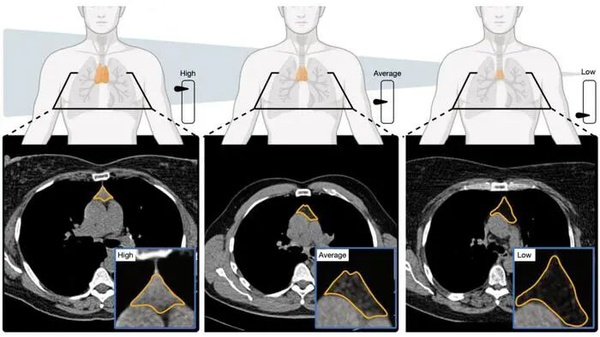

有了充足的数据后,研究团队就开始“遇事不决,机器学习”了。他们利用机器学习方法分析了CT扫描获取的胸腺图像,并分析胸腺的大小、形态和组织结构,构建出了胸腺健康评分(thymic health score)。这个评分从0到1,0代表胸腺完全脂肪化,彻底退化,失去了原有的功能;1代表胸腺高度健康。紧接着,研究人员按照胸腺健康评分开始给受试者的胸腺健康进行排名,并按照排名位次赋予胸腺健康值(thymic health values)。这个值从0到100,越高代表胸腺的健康排名越高。比如胸腺健康值是60,则代表胸腺健康程度领先60%的人。

麻省总医院的研究人员开发了一个深度学习模型,可以通过CT扫描评估胸腺的健康状况。本土从左到右分别为高、中、低胸腺的健康状况。图片来源:Mass General Brigham/Nature

研究人员按照胸腺健康值将人群划分成了低中高三组,分别对应胸腺健康值为0-25,25-75和75-100。结果发现,评分较高的组和较低的组相比,全因死亡率大约会低50%,心血管疾病死亡率下降63%,肺癌发病率也减少了36%。就算调整年龄等其他健康因素后,这些关联性仍具有显著的统计学意义。